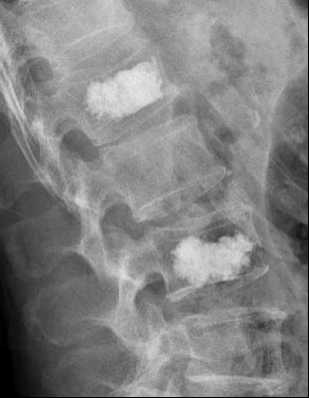

圖 3術(shù)后拍片